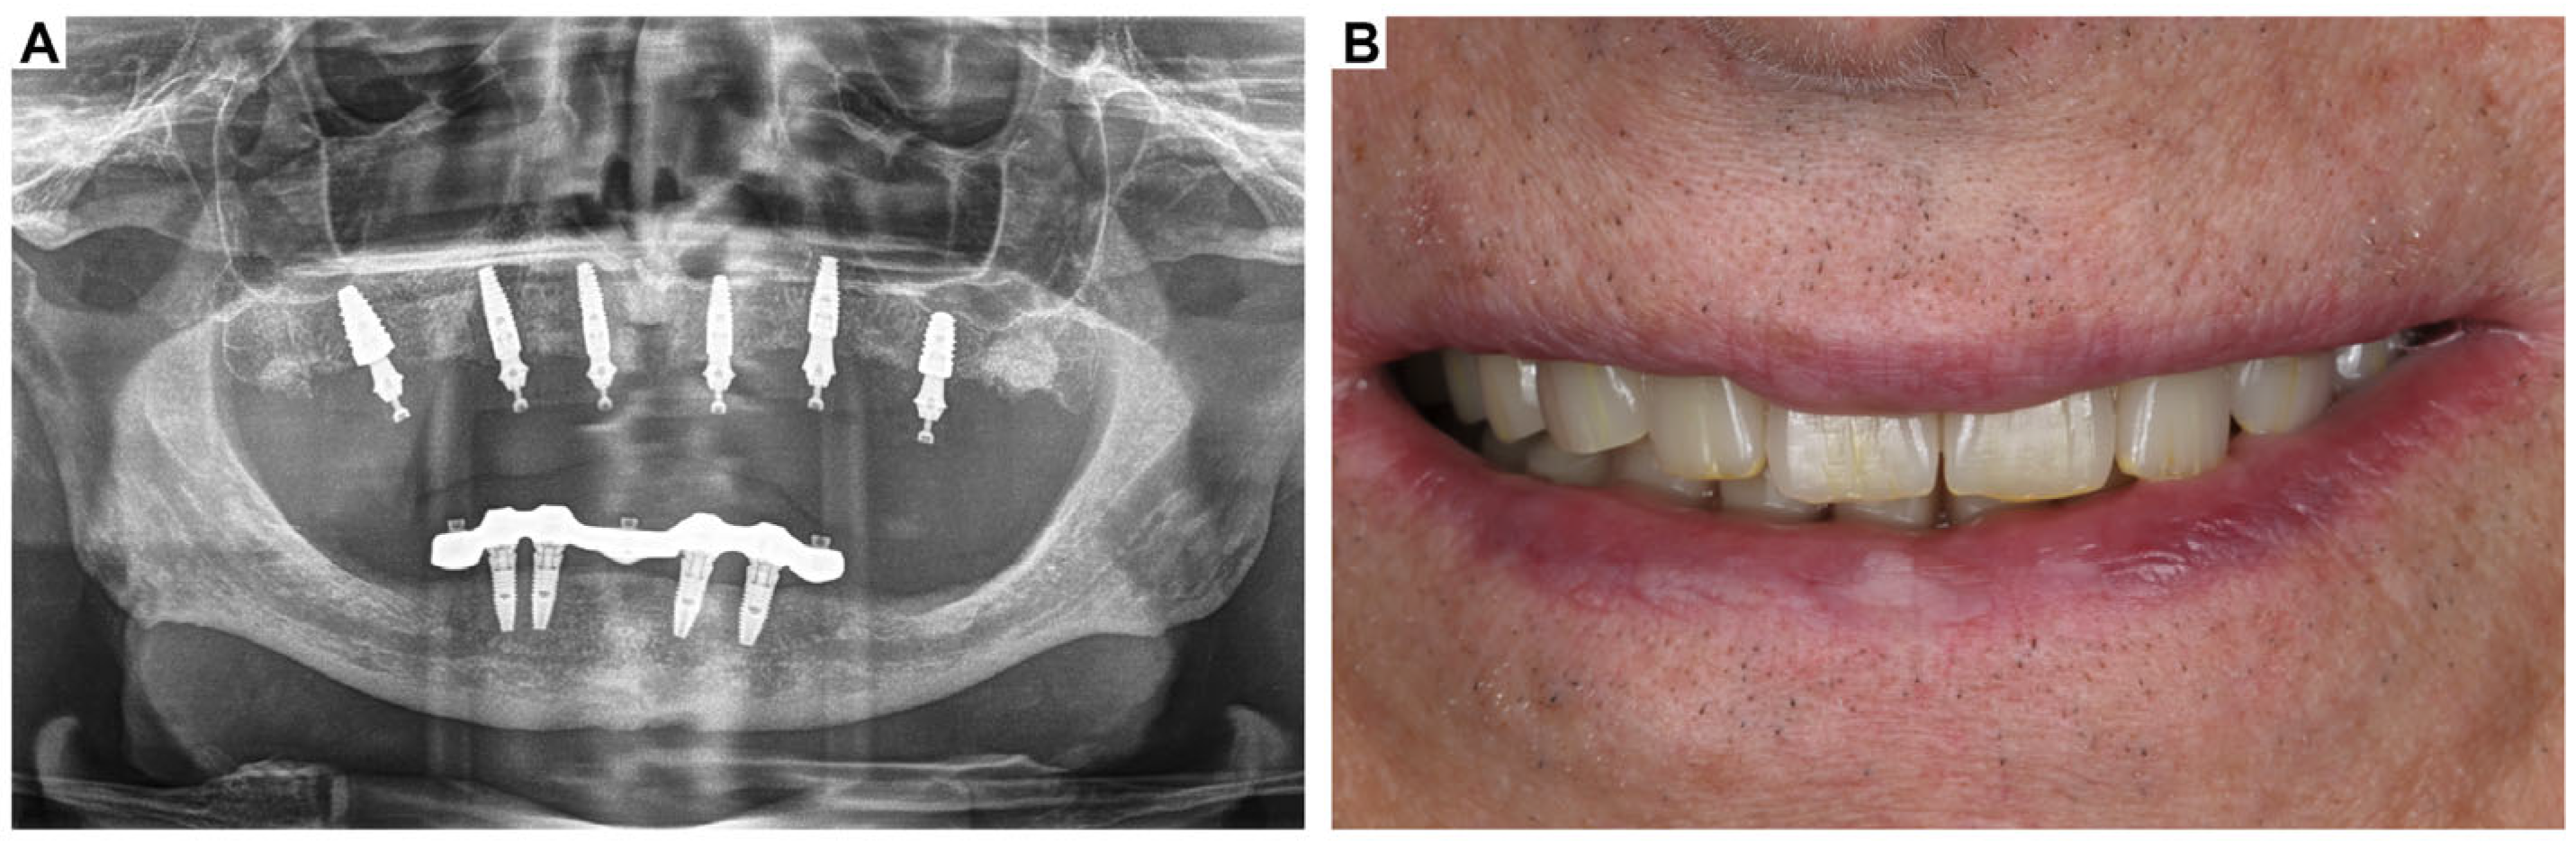

3. Clinical Cases Presentation of Advanced Implant Surgeries

3.1. Case Report-1